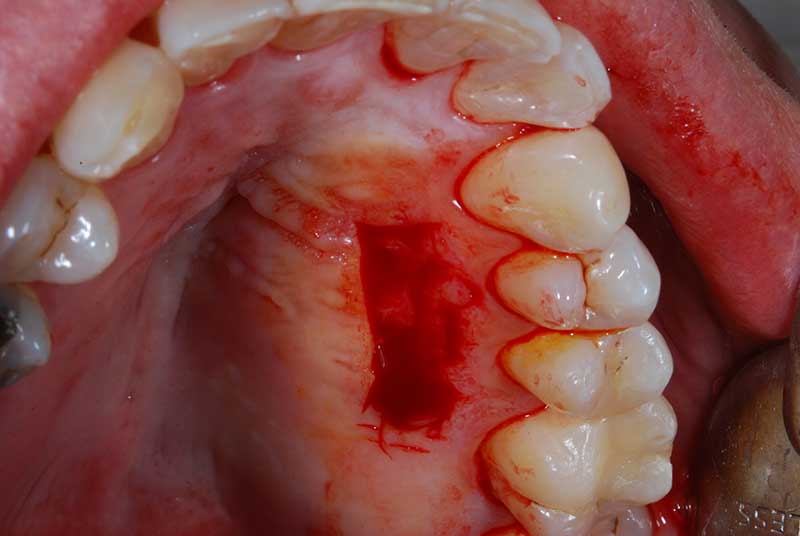

Lembo libero per correggere una recessione gengivale